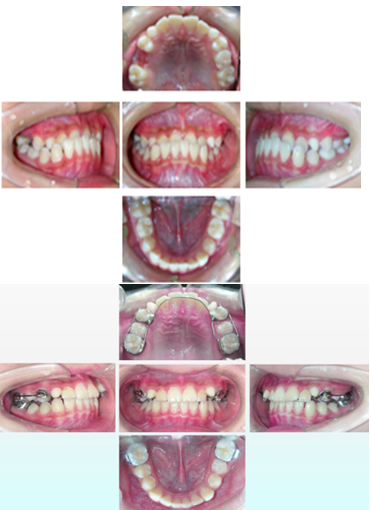

功能矫治前中后合像对照: